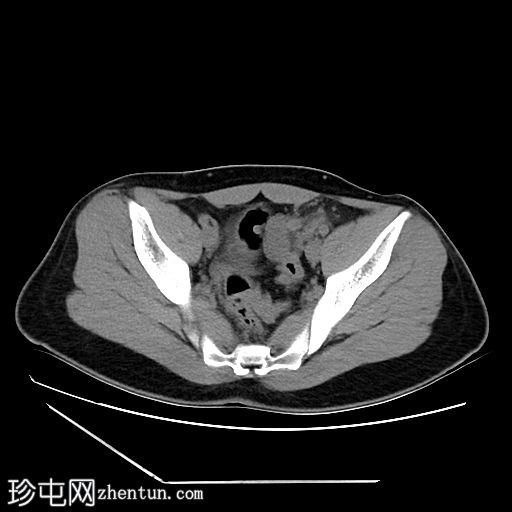

轴位增强扫描

动脉期

2.jpg

盆腔左侧可见一形态良好的子宫样结构(57 x 17毫米),开口于前列腺尿道。

右侧睾丸位于盆腔右侧,膀胱与直肠之间。大小:56 x 29 毫米。

左侧睾丸位于盆腔中线左侧,膀胱上方,子宫底旁。该结构附着于从左侧腹股沟管延伸出的索状结构上。大小:38 x 22 毫米。

患者有双侧隐睾病史。CT和MRI图像显示发育良好的子宫和两个睾丸,均位于盆腔内。子宫内膜腔开口于前列腺尿道。